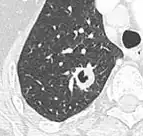

Thin slice and maximal intensity projection of a lung nodule, the latter better visualizing vascular convergence.[9]

• Vascular convergence is where vessels converge to a nodule without adjoining or contacting the edge of the nodule, and is mainly seen in peripheral subsolid lung cancers.[9] It reflects angiogenesis.[9]